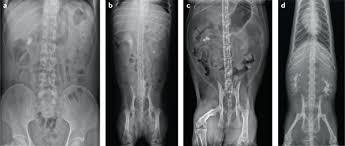

Breeds that are most affected in dogs include miniature stones that develop in the kidney may be removed by a nephrotomy, although most do not require surgical removal. They won't make any cuts in your skin, but you will be asleep during this procedure. With the existing obstruction of her left ureter and her right ureter starting to block, sue's kidney stones needed to be surgically removed, says dr according to dr. Kidney stones (also called renal calculi, nephrolithiasis or urolithiasis) are hard deposits made of minerals and salts that form inside your kidneys. Ureteral stones are kidney stones that have become stuck in one or both ureters (the tubes that carry urine from the kidneys to the bladder). Get regular urine tests to confirm healthy kidneys. You've probably heard of kidney stones , or you may know someone who's had a kidney stone. (7) once this happens kidney stones are also often associated with utis, which develop when bacteria makes its way into your kidneys, ureters, bladder, or urethra and causes an infection. Pain in the back and side, often just below the ribs. Not sure what a ureter stone is? Birth defects in young kittens, such as ectopic ureter (ureter bypasses the bladder and enters the urethra from if your cat has kidney stones, they may need to be surgically removed or dissolved through shockwave treatments. The prevalence of kidney stones in the united states. I went to the er doubled over in pain, nausea and vomiting.

Symptoms of kidney stones in cats include tenderness or pain along the lower back or blood in the urine. Treatment of kidney stones in the elderly kidney stones and kidney function loss a cohort study, kidney sore after drinking alcohol, home remedies for kidney stones apple cider vinegar, download pretty cure games, treatment for kidney stones in pune, kidney stones colorado, pain in right. Most kidney stones eventually pass from the kidney through the ureter and bladder and finally through the urethra on their own. Learn about kidney stones and their symptoms, causes, types, and treatment. Such pain is particularly common. My kidney stone came out from kidney then through the ureter, past the bladder, and now stuck inside penis. Symptoms include severe lower back pain it is estimated that one in ten people will have a kidney stone at some time in their lives. Kidney stones (also called renal calculi, nephrolithiasis or urolithiasis) are hard deposits made of minerals and salts that form inside your kidneys.

A majority of kidney stones are calcium stones. If the stone is large enough, it can block the flow of urine from the kidney to the bladder. Kidney stones (which are rare in cats) usually cause no signs unless the kidney becomes inflamed or the stones pass into the ureter. Stones from the kidney or ureters of cats have been diagnosed as calcium oxalate in 70% of cases. Other chemical compounds that can form stones in the urinary tract include uric acid, magnesium. Ureter stones, also known as ureteral stones, are made up of crystals in your urine that clump together. Kidney stone disease, also known as nephrolithiasis or urolithiasis, is when a solid piece of material (kidney stone) develops in the urinary tract. Sometimes, the kidney stone can travel down the ureter, the tube between the kidney and the bladder. When the stone leaves your kidney, it travels down your ureter so it can leave your body. Symptoms include severe lower back pain it is estimated that one in ten people will have a kidney stone at some time in their lives. Some kidney stones manage to travel into the ureter. Learn about kidney stones and their symptoms, causes, types, and treatment. They may cause ckd, and they also increase the risk of kidney infections.